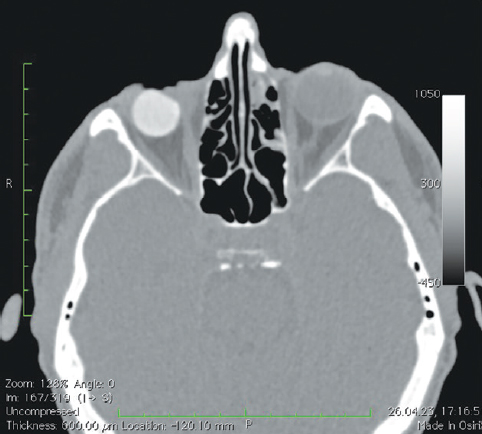

Рис. 7. Пациентка, 32 года. 3 года после операции с имплантацией эндопротеза с изменённой геометрией. МСКТ-исследование глазниц

Fig. 7. Patient, 32 y. o. 3 years after surgery with implantation of an endoprosthesis with modified geometry. MSCT of the socket

При анализе рентгенологических изображений после выполнения МСКТ-диагностики у всех обследованных пациентов по описанному ранее алгоритму [16] нами было выявлено изменение размеров и геометрии орбитальных сфер в виде «срезанной» части (рис. 8). Параметры изменённой части, как и размеры самих имплантатов, были различны (табл. 1–3). Исходные параметры (диаметры) орбитальных сфер — 18, 19 и 20 мм. При компьютерно-томографическом исследовании на полученных изображениях мы анализировали размеры имплантированных материалов, определяя объём вкладышей через радиус и высоту срезанной части по формуле: V = 1/3πh2(3r – h), где π — константа, равная 3,14; r — радиус шара; h — высота шарового сегмента имплантата.

Анализируя полученные данные, мы установили, что размеры изменённой геометрии имплантированных орбитальных вкладышей отличались, потери объёма при исходном диаметре 20 мм составили в среднем 0,4038 см3, при диаметре 19 мм — 0,340 см3, при диаметре 18 мм — 0,298 см3 (рис. 7–11).

В мягких тканях вокруг изменённых имплантированных сфер нами выявлены уплотнения, без признаков кальцинации и деструкции стенок орбиты (рис. 7, 8). Кроме того, у одной пациентки было отмечено не только изменение геометрии сферы в виде срезанной части (рис. 10, а), но и наличие множества фрагментов полимерного материала идентичной рентгенологической плотности. Эти фрагменты имплантата находились за задним полюсом полимерного вкладыша в мягких тканях до вершины орбиты (рис. 10, b).